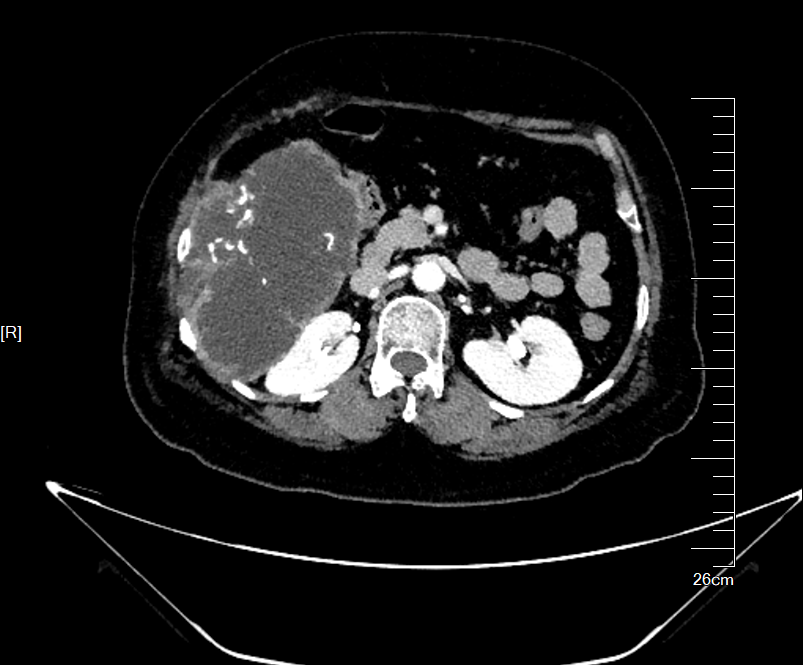

术前CT评估肿物与周围脏器关系,横截面与冠状面

影像检查显示,肿物起源于第7,8肋骨,沿胸腹壁蔓延累及第7至第11肋,上界与肝脏S5、S6段分界不清,内侧包膜紧贴右侧结肠,后方逼近右肾。“患者首次手术已切除部分肋骨,此次复发范围更广、侵袭更深,既要确保肿瘤完整切除(R0切除),又要最大限度保护重要脏器,需要多学科专家协作和新技术手段保驾护航。”骨科王伟东副主任在初次讨论时指出了本案例的关键节点。